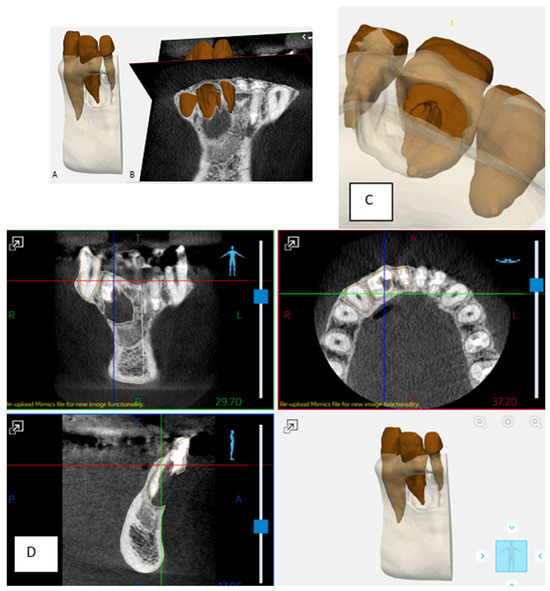

2.1. Pretreatment Planning

- The comparison between the use of 3D printing and milling with the use of Materialise software, as used in the current study, was profiled in a study by Kachhara et al. They concluded that an exact tooth replica can be created to assist in treatment planning [26]. The ability of the clinician to view a 3D model versus manipulating a CBCT image in the axial, sagittal, and coronal views, is beneficial to appreciating the fine detail of the unique root anatomy. The exact replica is produced to a high level of detail that can be directly viewed. Being able to handle the physical model provides an opportunity to manipulate and observe the model and appreciate the unique characteristics of the tooth and root anatomy when conceptualizing the proposed nonsurgical and surgical endodontic treatment.